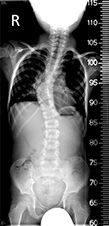

A veleszületett gerincferdülés tekintetében

Congenitalis scoliosis (veleszületett gerincferdülés) esetén a gyermekeket általában konzervatív úton (fűző, gyógytorna, egyéb fejlesztés) nem kezelik, ezek nem szükségesek (nem hatásosak). Dévény-torna, más terápia nem szükséges, hiszen ezek a csontos struktúrát nem befolyásolják. Alapvetően mindig a gerincsebész szakember egyénileg dönt a kezelésről. Érdemi kezelés (megfigyelés) a gyermek stabil állása után, egyéves kor körül kezdhető.

A kezelés menete, kezelési módok